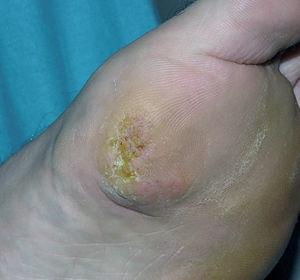

Un paciente varón de 36 años, de origen rumano, sin antecedentes de interés, acudió a consultas de dermatología por la presencia de una lesión en planta de pie izquierdo. Refería que a los 17 años comenzó con una hiperqueratosis, de crecimiento lentamente progresivo y que le molestaba al caminar. Hace 4 años se le realizó una pequeña extirpación en su país de origen, pero el paciente no aportaba informes. Hace 3 años reapareció nuevamente una lesión, que fue creciendo lentamente, y era dolorosa al andar, motivo por el que consultaba. En la exploración física presentaba una placa hiperqueratósica en la región plantar del primer metatarso, no ulcerada, de límites mal definidos y de aproximadamente 2 x 2 cm (fig. 1). Con el diagnóstico clínico de carcinoma verrucoso, se realizó biopsia en la que se observaba una epidermis hiperqueratósica y sin alteraciones aparentes, mientras que en la dermis y grasa se ponía de manifiesto una proliferación tumoral formada por nidos de células endoteliales de aspecto epitelioide redondeadas y poligonales. El citoplasma era eosinófilo y contenía luces intracitoplasmáticas, algunas de las cuales estaban llenas de hematíes. En ciertas áreas, las células se disponían formando canales vasculares. No se observaban figuras de mitosis ni de atipia nuclear (fig. 2). La inmunohistoquímica fue positiva para CD34 y factor VIII (fig. 3) y negativa para S-100 y panqueratinas (fig. 4). Con estos datos se realizó el diagnóstico de HEE.

Fig. 1.--En la región plantar del primer metatarso se observa una placa hiperqueratósica mal definida, de aproximadamente 2 x 1,8 cm, no infiltrada ni ulcerada.